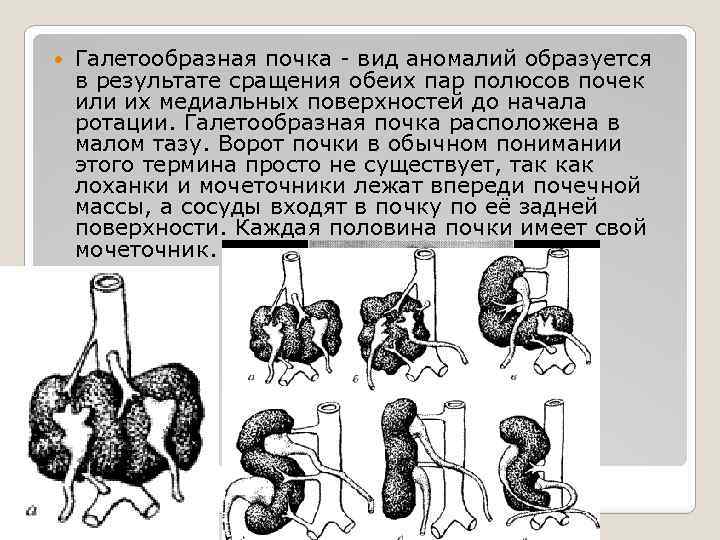

Галетообразная почка - вид аномалий образуется в результате сращения обеих пар полюсов почек или их медиальных поверхностей до начала ротации. Галетообразная почка расположена в малом тазу. Ворот почки в обычном понимании этого термина просто не существует, так как лоханки и мочеточники лежат впереди почечной массы, а сосуды входят в почку по её задней поверхности. Каждая половина почки имеет свой мочеточник.

Галетообразная почка - вид аномалий образуется в результате сращения обеих пар полюсов почек или их медиальных поверхностей до начала ротации. Галетообразная почка расположена в малом тазу. Ворот почки в обычном понимании этого термина просто не существует, так как лоханки и мочеточники лежат впереди почечной массы, а сосуды входят в почку по её задней поверхности. Каждая половина почки имеет свой мочеточник.